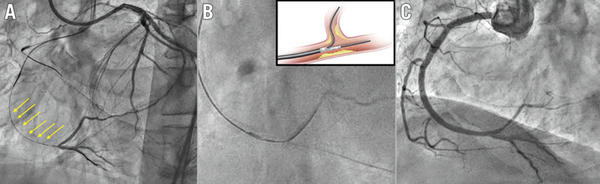

Figure 1. Dual lumen microcatheter in bifurcation lesions associated with CTO. Example of a right coronary artery CTO with a bifurcation at the distal cap and a long proximal dissected segment (arrows). A) Wire into the true lumen of the posterior descending artery. B) Dual lumen microcatheter to pass a new guidewire into the posterolateral branch. C) Final angiographic result after provisional stenting. CTO: coronary chronic total occlusion.

Source: EuroIntervention Journal